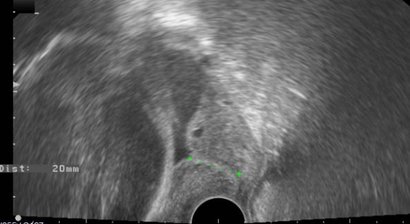

Betreuung nach Frühgeburten

Frühgeburten sind das Hauptproblem der modernen Geburtshilfe und verantwortlich für 70% der perinatalen Mortalität sowie 80-90% der neonatalen Morbidität. Obwohl ca. 10% aller Geburten als Frühgeburt zu definieren sind (Geburt vor der abgeschlossenen 37. SSW), konzentrieren...